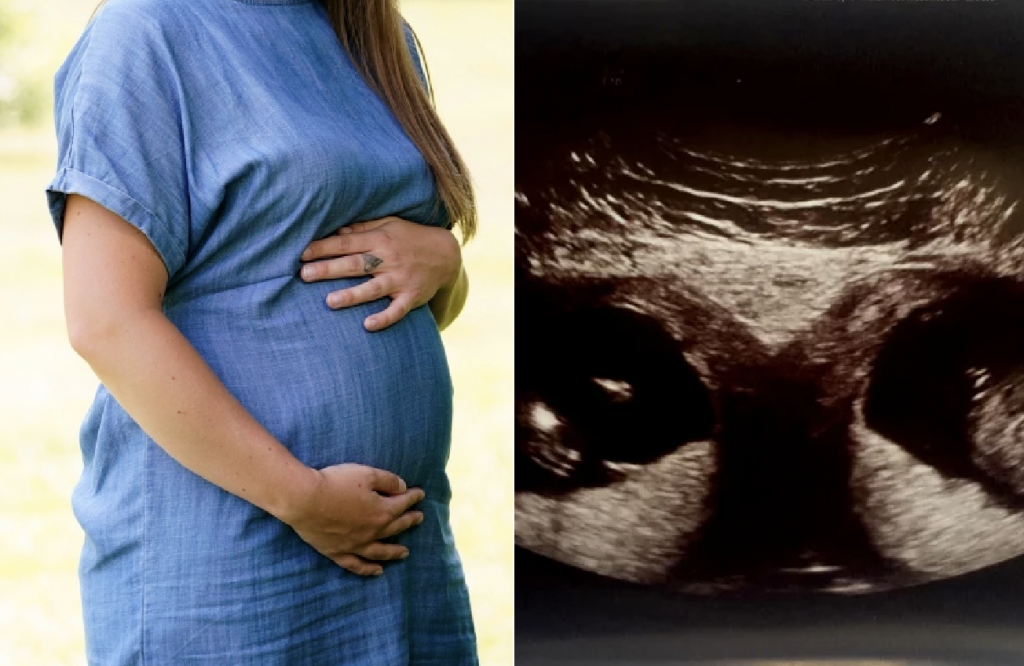

When she went in for her 12-week ultrasound, she was looking forward to hearing some updates about her baby’s growth. But she certainly wasn’t expecting doctors to be stunned and leave her speechless. The pregnant woman Kelly and her partner Joshua were amazed when they discovered they were expecting another child. But, little did they know that they were about to get an even bigger surprise. At her 12-week pregnancy scan, she learned she’s carrying two babies — in separate w0mbs. “The condition itself is quite rare, but they went on to tell me that it was a one in a 50 million chance for me to conceive twins in each womb,” the lucky mother said.

Pregnant Kelly Fairhurst discovered that she has two wombs, and each one of them is carrying a baby. The then-28-year-old mom of two said that she found out about the two wombs when she went for her 12 weeks ultrasound scan. Kelly says that she was shocked about the two wombs, and the fact that each womb is carrying a baby is crazy to her. The condition of developing two uteruses is known as uterus didelphys. Experts say that a uterus develops from two small tubes that later join to form one uterus, but if the two tubes do not join, they become double uteruses.

Although there are women who have double uteruses, having a situation where both uteruses have babies growing in them at the same time is quite rare. Kelly says that doctors told her that the chances of having such occurrences were one in 50 million. The main challenge for Kelly would be going into labour twice, and she wants to avoid this by having a Caesarean birth. Kelly, who has two daughters aged three and four years, says that both of her girls were born prematurely. Although they have twin history in her family, Kelly never imagined that she would have twins, especially in different wombs!

According to the Sun, doctors say that there is a high possibility that Kelly would have identical twins. Even though the news of having two wombs was shocking to Kelly and her 34-year-old boyfriend Joshua, Kelly says that she feels grateful that she would have two amazing babies. During her second pregnancy, she had been told that she could be having a bicornuate uterus meaning that her uterus had not fully developed. However, she was surprised to discover that she has two!